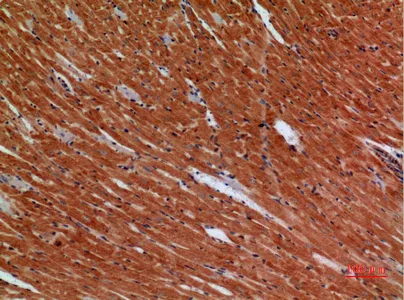

Apaf-1 Rabbit Polyclonal Antibody

Cat: APRab06988

Size1:50μl Price1:$118

Size2:100μl Price2:$220

Size3:500μl Price3:$980

Angptl1 Rabbit Polyclonal Antibody

Cat: APRab06897

Size1:50μl Price1:$118

Size2:100μl Price2:$220

Size3:500μl Price3:$980